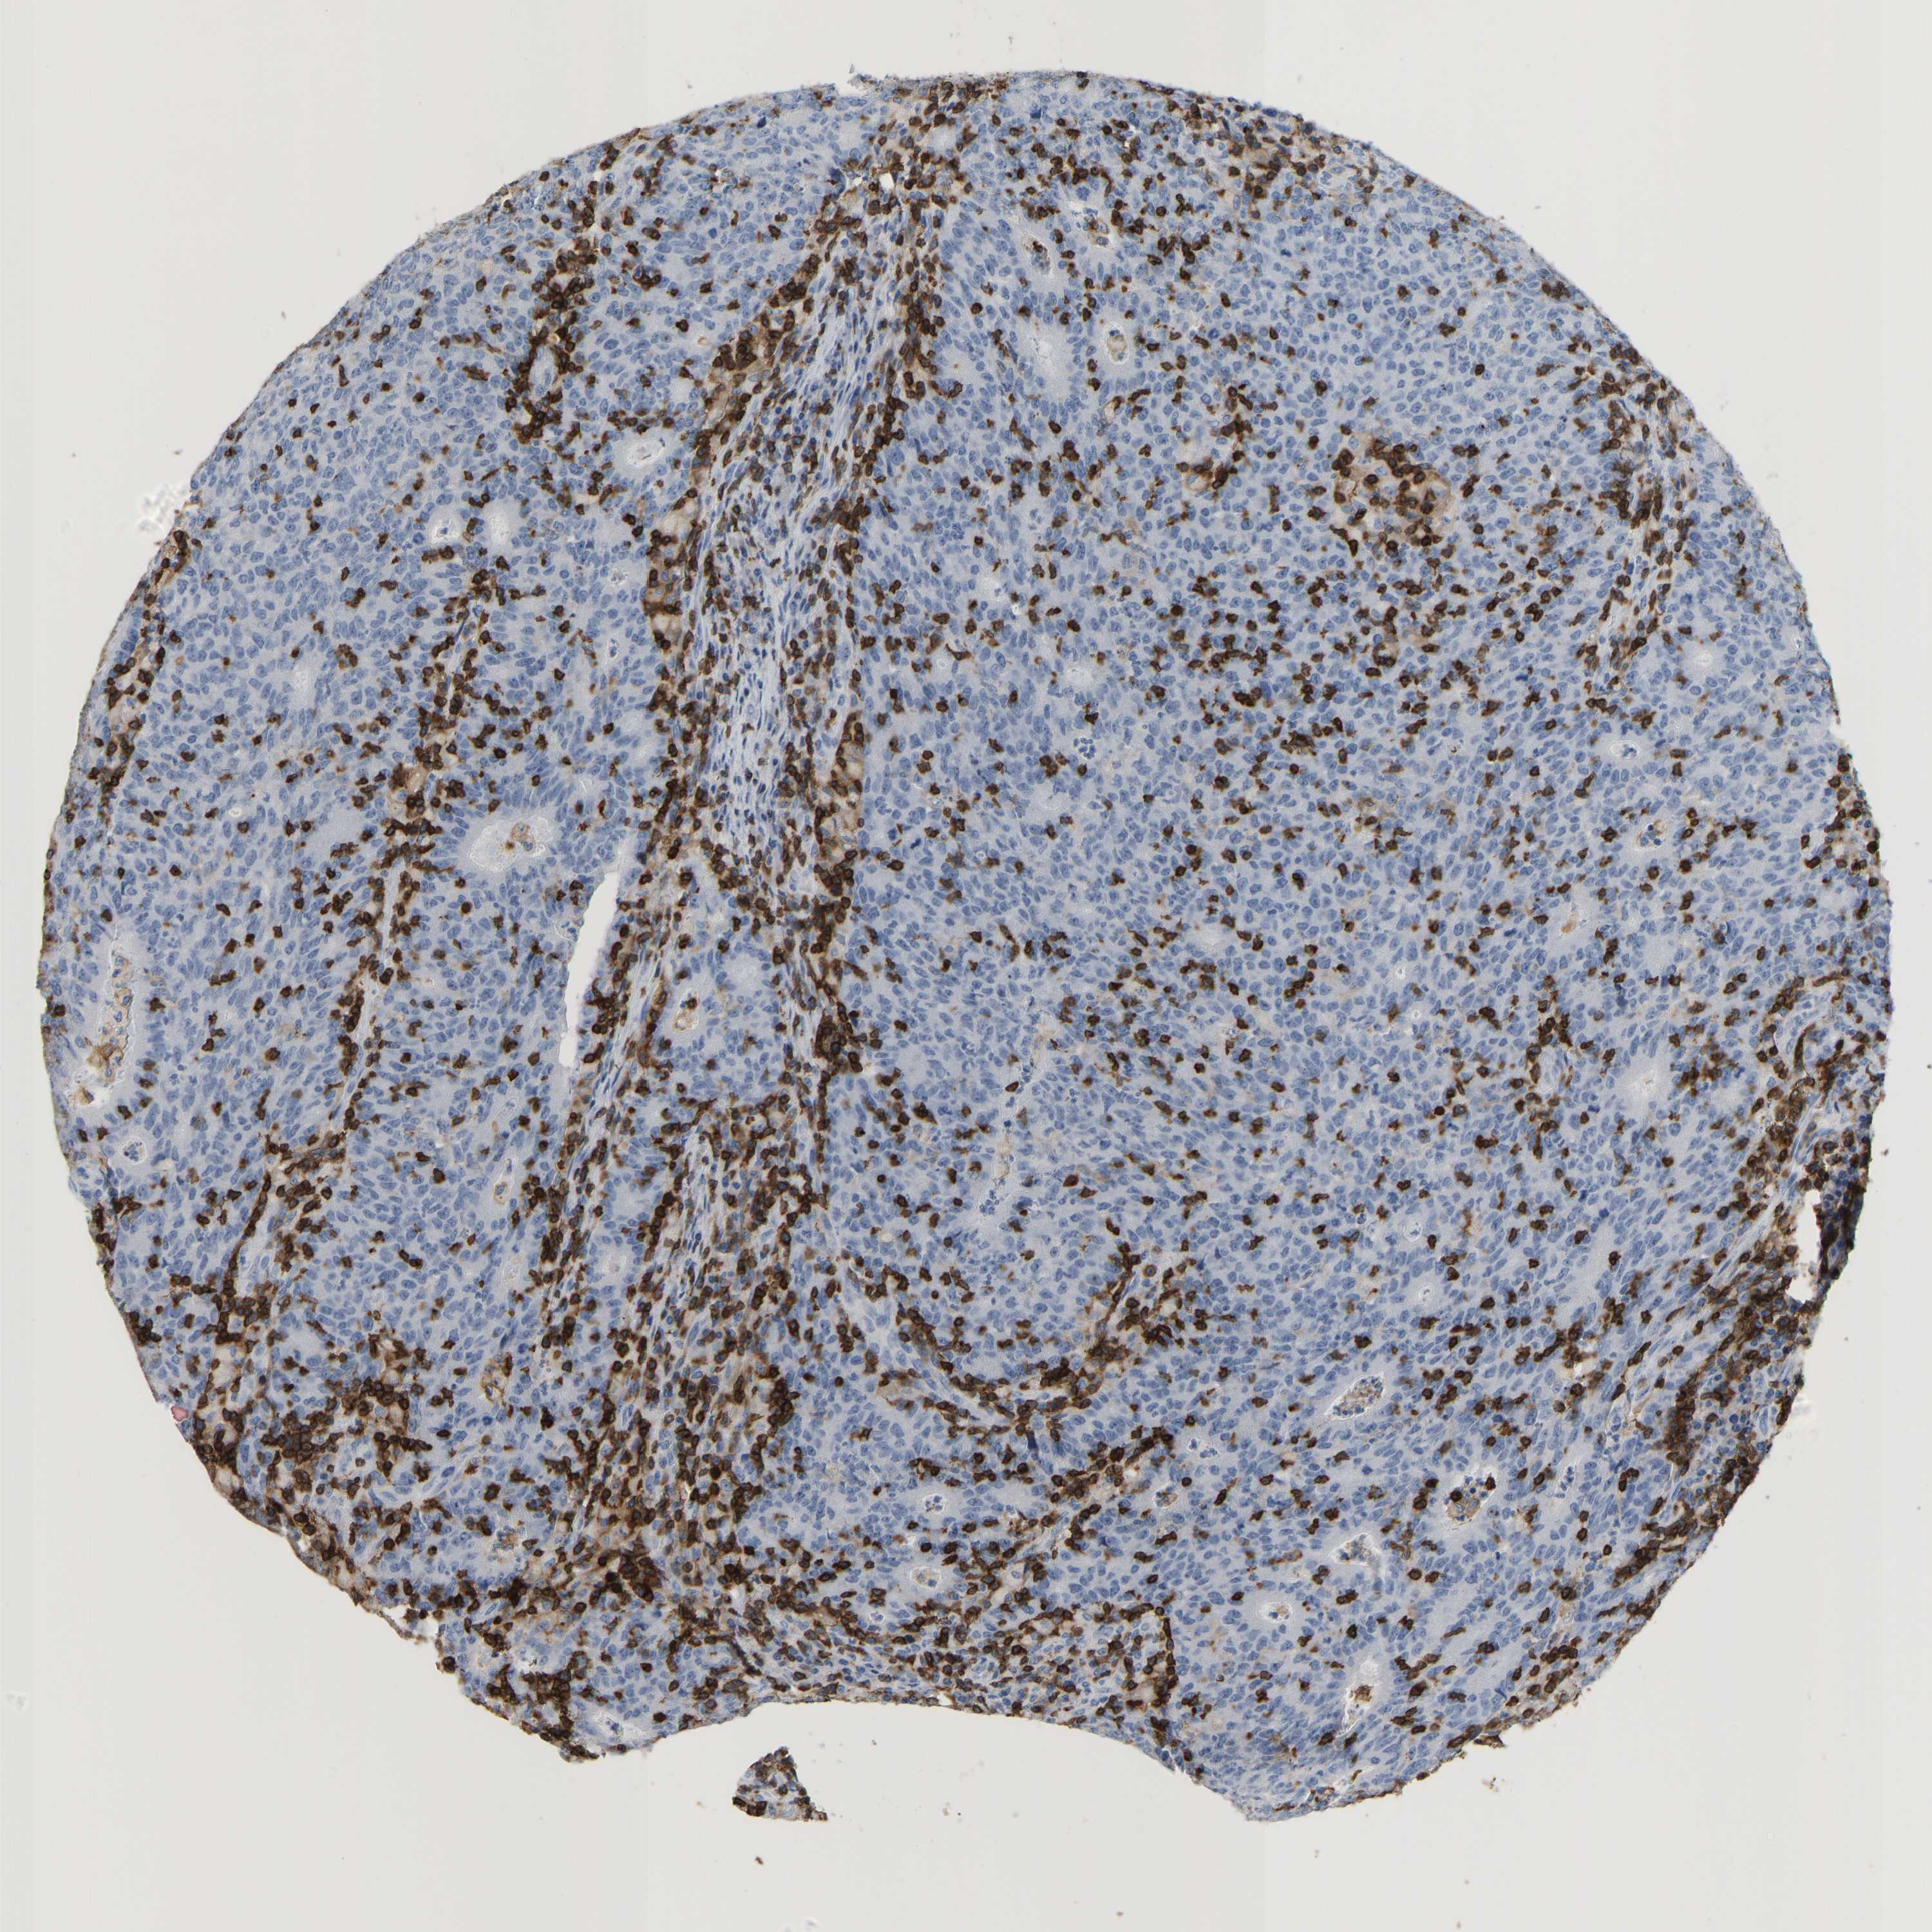

CANCER COLORECTAL CANCER Show tissue menu

COAD TCGA COAD VALIDATION READ TCGA READ VALIDATION PROTEIN COAD CPTAC PROTEIN EXPRESSION

ANTIBODIES

AND

VALIDATION